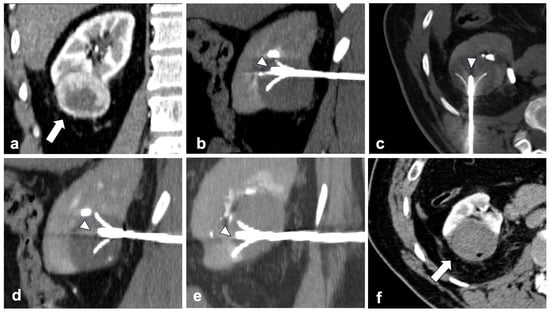

2.2. Procedures

2.3. Ablative Devices and Techniques

2.4. Imaging Guide